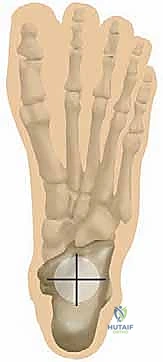

عملية تثبيت مفصل الكاحل والقدم الخلفية، والمعروفة طبياً بـ (Tibiotalocalcaneal Arthrodesis)، هي إجراء جراحي معقد يهدف إلى دمج (لحام) ثلاثة عظام رئيسية معاً لتكوين كتلة عظمية واحدة صلبة وغير متحركة. هذه العظام هي: عظمة الساق الكبرى (Tibia)، وعظمة الكاحل (Talus)، وعظمة الكعب (Calcaneus).

لفهم أهمية هذه الجراحة، يجب أولاً فهم التشريح المعقد لهذه المنطقة. يتكون الجزء الخلفي من القدم والكاحل من مفصلين رئيسيين:

- مفصل الكاحل (Tibiotalar Joint): وهو المفصل الذي يربط بين عظمة الساق وعظمة الكاحل، وهو المسؤول عن حركة القدم لأعلى ولأسفل.

- المفصل تحت القعب (Subtalar Joint): وهو المفصل الذي يقع أسفل عظمة الكاحل ويربطها بعظمة الكعب، وهو المسؤول عن حركة القدم للداخل والخارج (الانقلاب الداخلي والخارجي) ويساعد في التكيف مع الأسطح غير المستوية.